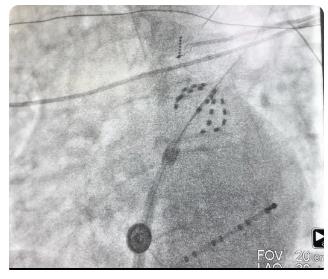

上图为X线下farapulse导管的两种形态:网篮状(左)和花瓣状(右)